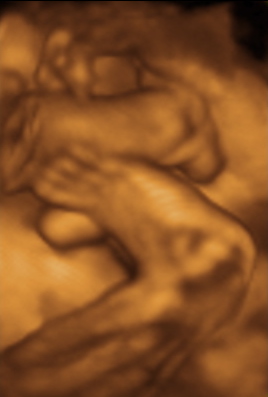

35 week Ultrasound

Friday, July 2nd, 2010

She weighs 5 pounds (2.25kg) and we think she’s pretty cute.